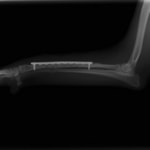

症例3:キルシュナーワイヤーのピンニングによる整復

ペルシャ猫 11ヶ月齢 雄

他院にて左大腿骨遠位の成長板骨折(salter-harrisⅠ型)が認められており、治療相談を目的として来院。当院にて、キルシュナーワイヤーを用いたピンニングにより骨折部位の整復を行いました。術後の経過は良好で、現在も経過観察中です。

術前レントゲン

術後レントゲン

機器

Arthrex社のターゲティングデバイスを用いてピンニングの位置を調整することで、確実な固定を行っています。当院ではこの手術器具以外にも、人の手術にも使用される様々な器具を導入し、手術精度を高め、また医療メーカーと新しい器具の開発、試作にも取り組んでおります。